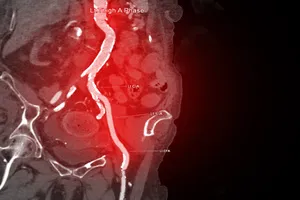

허혈성 심장질환은 심장에 혈액을 공급하는 관상동맥이 좁아지거나 막혀 심장 근육이 충분한 산소를 공급받지 못하는 질환입니다. 마치 자동차 엔진에 기름이 부족하여 제대로 작동하지 못하는 것과 같이, 심장도 혈액이 부족하면 제 기능을 다하지 못하게 됩니다. 이러한 현상은 주로 혈관 내벽에 콜레스테롤 등이 쌓여 혈관이 좁아지는 동맥경화로 인해 발생합니다.

허혈성 심장질환은 주로 동맥경화라는 만성 질환으로 인해 발생합니다. 동맥경화는 혈관 내벽에 콜레스테롤과 지방 등이 쌓여 혈관이 좁아지거나 막히는 현상으로, 이는 심장으로 가는 혈류를 방해하여 허혈성 심장질환을 유발합니다.

막힌 혈관 부위에 작은 절개를 하고 도관을 삽입하여 풍선으로 좁아진 부위를 넓히거나 스텐트를 삽입하여 혈관을 지지하는 시술입니다.